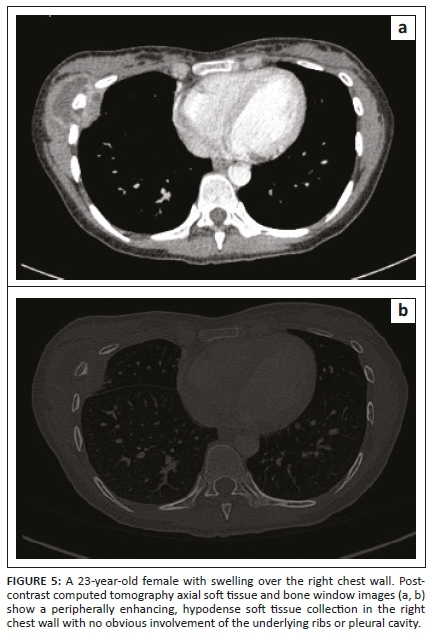

Tubercular involvement of ribs presents as either bony erosions with disruption of the cortical margin or frank destruction, with adjacent abscess formation.6,7 There may be focal expansion of the involved rib with or without periosteal reaction. Tuberculous abscesses of the chest wall can involve the sternum, costochondral junctions, rib shafts, costovertebral joints and the vertebrae.7 They are most frequently found at the margins of the sternum and along the rib shafts. A tuberculous retromammary abscess appears as a focal, smoothly marginated, inhomogeneous, hypodense lesion with a surrounding enhancing rim.13 A direct fistulous communication with the pleura or a destroyed rib fragment found in a tuberculous abscess can be helpful in differentiating it from other types of retromammary abscess.13,14 In the case of chest wall TB, the detection of underlying pleuro-parenchymal disease is often helpful in suggesting the diagnosis.3

Our patients demonstrated similar imaging findings, better documented on CT as lytic destruction or erosion of the sternum, clavicle, acromion, ribs and mandibular condyle. Soft tissue collections were detected around the bony involvement and this was also demonstrated on USG, where accessible. Ultrasonography showed the abscess as a hypo-echoic collection with posterior acoustic enhancement and varying degrees of internal heterogeneity. Some authors have also highlighted the use of USG as a cost-effective and useful modality to assess rib destruction/irregularity and associated soft tissue abscess in chest wall TB.6 In addition, USG provides real-time guidance for obtaining a tissue sample for pathological confirmation. The need for image guidance in accurately obtaining the tissue specimen from deep-seated collections/pathology, which is not appreciated clinically, is an important aspect of management, as the histopathological demonstration of caseous necrosis in the granulomas and microbiological identification in culture provides definite evidence of TB.2